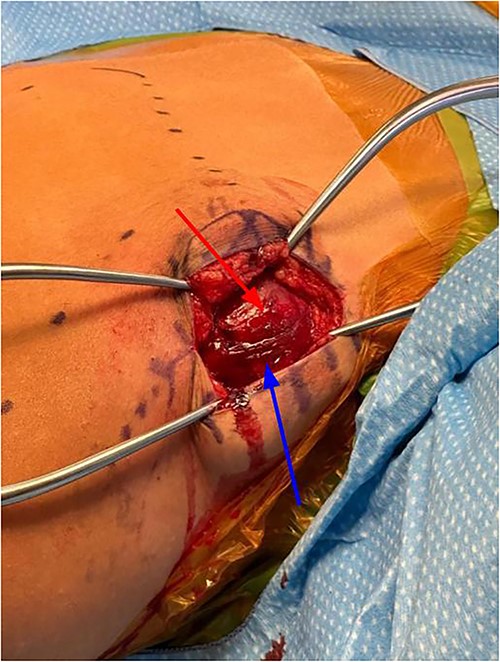

Subcutaneous tissue was divided with the electrocautery. Investing fascia over the trapezius was identified and the division between the superior and middle fibers of the trap was identified. The raphe between the superior and middle fibers was then bluntly spread in line (Fig. 3). We then encountered the superior aspect of the ventral lesion on the scapula (Fig. 4). Of note, the majority of levator scapulae fibers were medial to this lesion; however, the most lateral portion of the muscle was overlying the lesion. These lateral fibers were spread in line to expose the pedunculated mass. Blunt dissection was then taken circumferentially around the stalk of the mass to ensure all soft tissue had been freed from the area (Fig. 5). An osteotome was then carefully placed within the wound at the base of the stalk, and the tumor was then removed and sent to pathology for analysis. The stalk remnant was then filed down to a smooth and stable base with a rasp without any significant areas of potential irritation or prominence. The wound was then copiously irrigated with normal saline. Fluoroscopy images demonstrated complete resection of the bony tumor. There was no active bleeding within the wound. The fascia overlying the trapezius muscle and the skin were then closed.

Exposure after superficial dissection, middle trapezius fibers (top arrow) and superior trapezius fibers (bottom arrow).